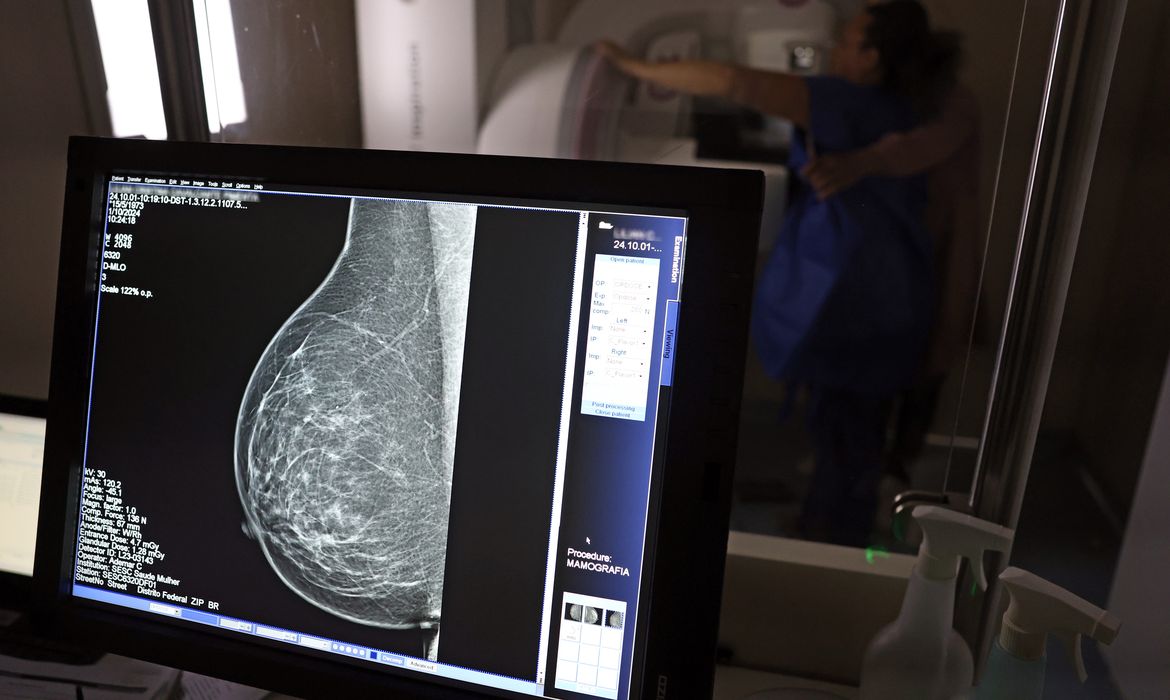

No mês de conscientização sobre o câncer de mama, um relatório destaca a importância de acesso igualitário ao rastreamento e tratamento da doença. Segundo o Atlas da Radiologia no Brasil, do Colégio Brasileiro de Radiologia e Diagnóstico por Imagem (CBR), o acesso aos mamógrafos ainda é um desafio. O país tem 6.826 equipamentos registrados, sendo 96% em funcionamento. Metade deles está disponível no Sistema Único de Saúde (SUS), responsável por atender 75% da população. Isso equivale a 2,13 mamógrafos por 100 mil habitantes dependentes do SUS. Na saúde suplementar, que cobre 25% da população, o cenário é mais favorável: 6,54 aparelhos por 100 mil beneficiárias, quase o triplo da rede pública. O Acre exemplifica essa disparidade — são 35,38 mamógrafos por 100 mil habitantes na rede privada, contra 0,84 no SUS. Há disparidades regionais. Roraima tem a menor proporção (1,53 por 100 mil), seguida do Ceará (2,23) e Pará (2,25). A Paraíba lidera o ranking (4,32), à frente do Distrito Federal (4,26) e do Rio de Janeiro (3,93). Segundo a coordenadora da Comissão Nacional de Mamografia do CBR, Ivie Braga de Paula, todos os estados têm número suficiente de aparelhos para o exame. Mas um conjunto de gargalos dificultam o acesso e geram subutilização. “Há problemas de informação, de comunicação, de acesso e logística, principalmente na Região Norte. Por exemplo, os mamógrafos ficam nas cidades mais centrais e a população ribeirinha não consegue chegar. Às vezes, tem que andar seis a sete horas de barco para fazer uma mamografia. Até nos grandes centros, as pacientes da periferia não têm informação suficiente e enfrentamdificuldades para marcar e chegar em um local com mamógrafo”, diz Ivie. O Brasil tem uma cobertura muito baixa de mamografias: 24%. O ideal recomendado pela Organização Mundial da Saúde é de 70%. Mesmo em lugares como o estado de São Paulo, que tem a maior concentração de mamógrafos do país, a taxa gira em torno de 26%. Em setembro, o Ministério da Saúde ampliou as diretrizes de rastreamento, recomendando que mulheres entre 40 e 49 anos realizem mamografias, mesmo sem sintomas. De acordo com o Instituto Nacional do Câncer (Imca), mais de 73 mil mulheres recebem o diagnóstico de câncer de mama anualmente no Brasil. “O que é efetivo na redução da mortalidade é você descobrir o tumor antes de ter sintoma clínico. Quanto menor o tumor, melhor para a gente descobrir o tratamento e maior a chance de cura. E a gente só consegue fazer isso com exames de imagem", diz Ivie. Ela explica que no caso de diagnóstico de um câncer de mama com menos de 1 cm, a chance de cura é de 95% em cinco anos, independentemente se ele é do tipo mais agressivo. "E esses tumores só vão ser detectados na mamografia. Essas pessoas que têm que ir fazer mamografia são mulheres saudáveis. Não são mulheres doentes”, acrescenta. Relacionadas Inca estima 73,6 mil novos casos de câncer de mama no Brasil em 2025 Ministério da Saúde passa a recomendar mamografia a partir dos 40 anos Câncer de mama: uma em cada três pacientes tem menos de 50 anos